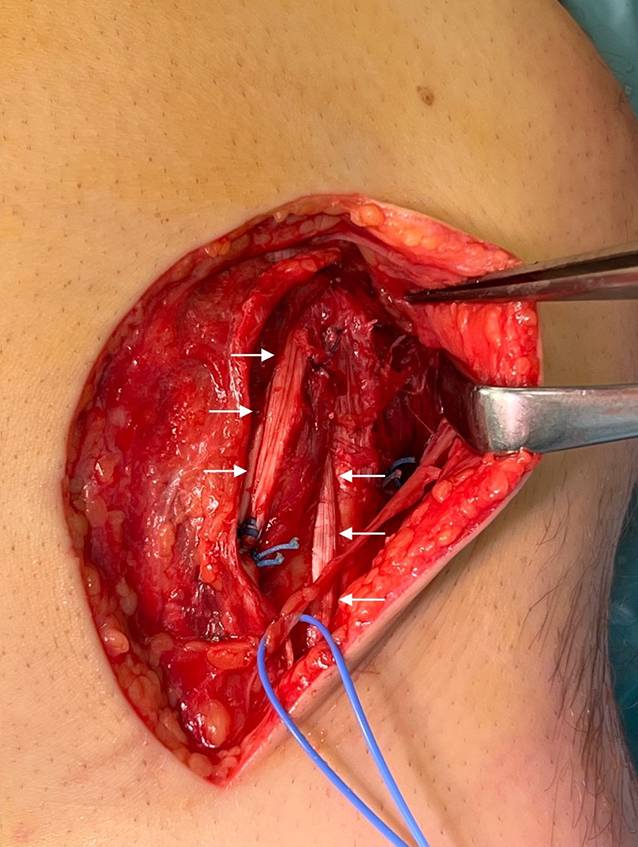

Abb. 4

Intraoperatives Bild einer kombinierten proximalen Verletzung des tiefen Seitenbands (dMCL) und des distalen Seitenbands (sMCL). a Anschlingen des dMCL. b Refixiertes dMCL. c Refixiertes sMCL distal. ac (Stern Ankerposition)

Operationstechnik bei akuter medialer Instabilität

In der Akutsituation kann insbesondere bei Avulsionsverletzungen die primäre Refixation mit Knochenankern angestrebt werden. Hier ist es wichtig, in der präoperativen Planung die genaue Lokalisation der Verletzung der einzelnen Bandanteile zu kennen, um dann einen adäquaten Zugang wählen zu können (Abb. 3). Es können der oberflächliche und tiefe Anteil des MCL jeweils proximal oder distal ausreißen. Speziell bei Außenrotationsverletzungen kommt aber auch eine distale sMCL-Ruptur in Kombination mit einer proximalen dMCL-Ruptur vor. Werden die Bandanteile an ihr jeweiliges Insertionsareal refixiert, kann meistens wieder eine adäquate Stabilität erreicht werden ([7]; Abb. 4). Dies sollte unter arthroskopischer Sicht und/oder Bildwandler überprüft sowie die freie Beweglichkeit des Kniegelenks (zumindest zwischen 0° und 120°) kontrolliert werden.